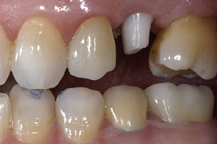

Ceramic Abutment connected to implant

Ceramic crown bonded to abutment

The adjacent images show how a ceramic abutment can enhance a ceramic crown by giving it a more lifelike appearance. Ceramic abutments have to be used with care, however, since their compressive strength is nowhere near that of titanium, gold or other noble metals. Most clinicians feel more comfortable using a metal prosthetic abutment in the posterior molar areas, due to the increased masticatory forces present in these areas.